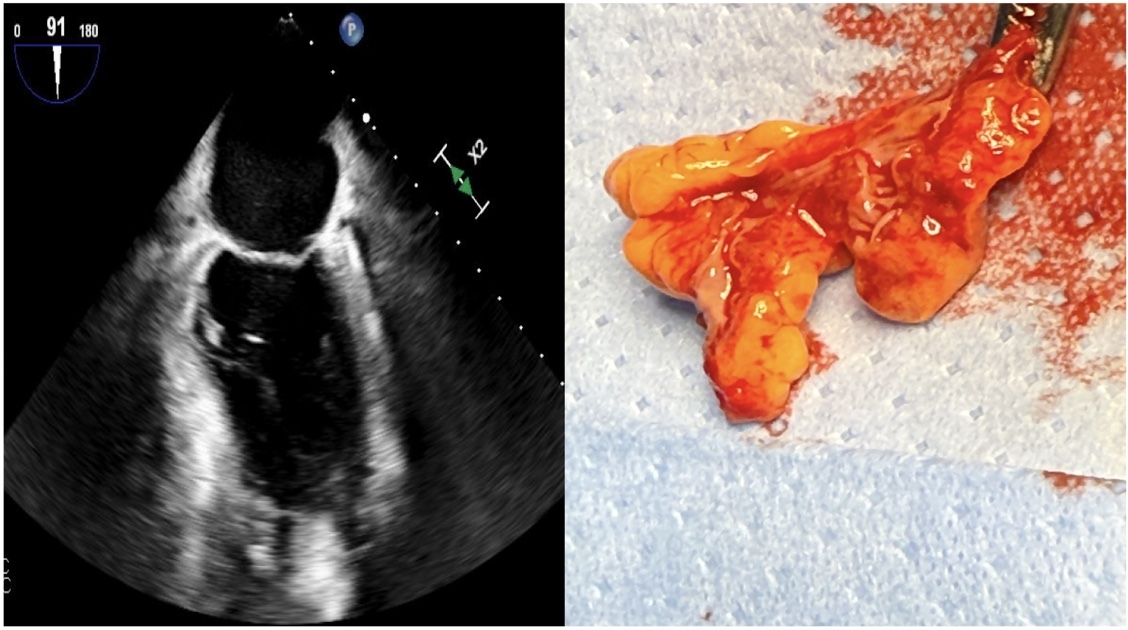

Case 2: A 60-year-old female with paroxysmal AF and hypertension, presented with non-ST-elevation myocardial infarction and was found to have triple vessel disease. She was planned for coronary artery bypass grafting (CABG), MAZE procedure, and LAA excision. Intraoperative TEE did not visualize any LAA, suggesting congenital absence of LAA. However, a LAA was seen intra-op, which was empty and collapsed due to the presence of complete membrane at the ostium without any fenestrations (Figure 2).

These cases illustrate that LAA membranes can rarely be present, which can be partial, fenestrated or complete. Presence of a complete membrane leads to a collapsed LAA, which can not be visualized on TEE mimicking congenital absence of LAA.